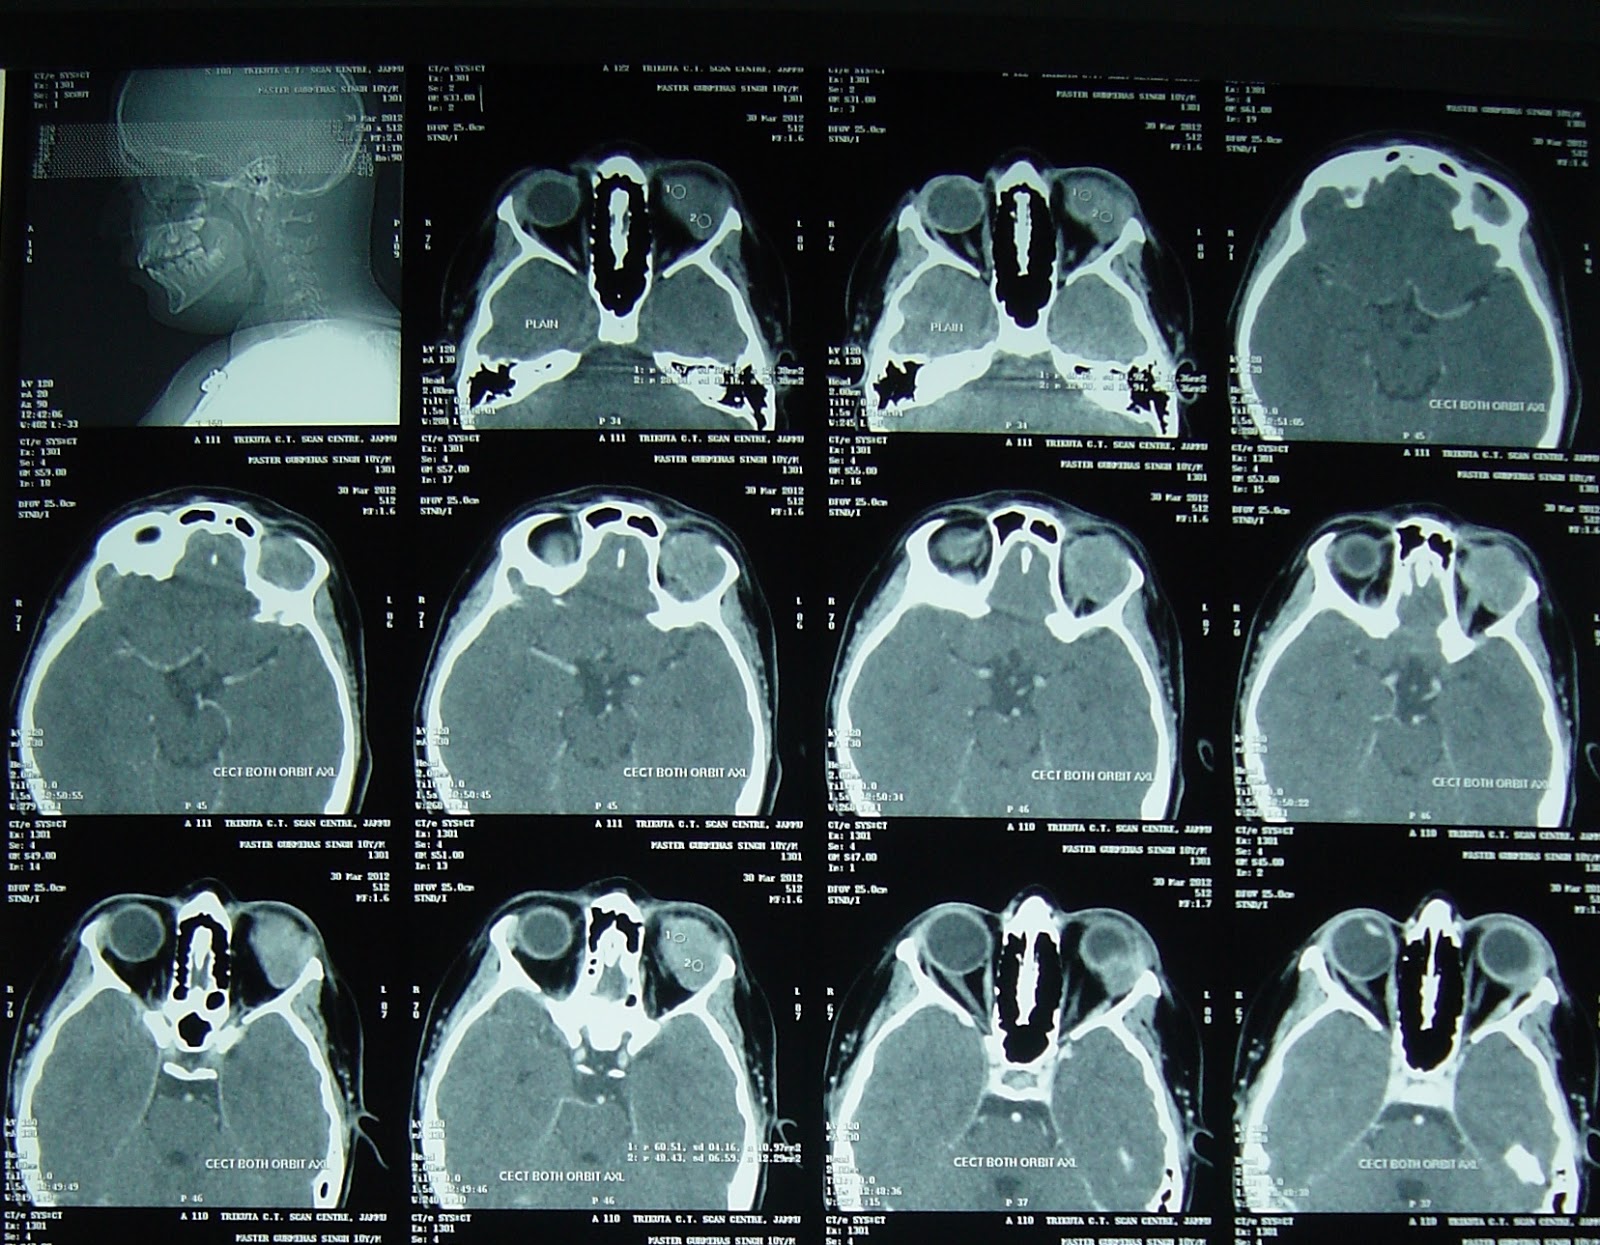

Neurosurgeon India: Orbital Rhabdomyosarcoma

neurosurgeon-india.blogspot.com

neurosurgeon-india.blogspot.com

rhabdomyosarcoma ct scan neurosurgeon india op pre